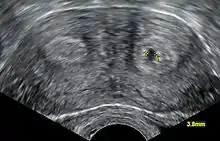

Aparte del examen físico, el doctor necesitará tomar imágenes para determinar las características de la malformación: Ultrasonografía ginecológica, resonancia magnética (MRI) pélvica o histerosalpingografía. Un histerosalpingograma no es considerado de utilidad debido a su inhabilidad para evaluar el contorno exterior del útero y distinguir entre un bicornio y un útero particionado. Adicionalmente una laparoscopia y/o histeroscopia pueden ser recetados. En algunos pacientes el desarrollo vaginal puede ser afectado. Al contrario de lo que pudiera pensarse, esta "malformación" no representa incomodidad alguna para la persona que la presente.